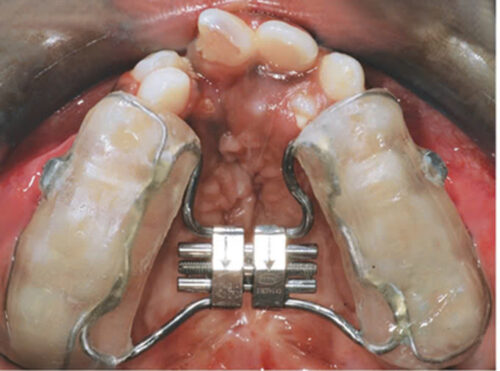

Chỉnh nha giúp nong rộng xương hàm trên, đưa răng về vị trí đúng, thuận lợi làm tiền đề cho phẫu thuật chỉnh hình xương hàm sau này giúp người bệnh đạt được tối ưu cả về chức năng và thẩm mỹ mang lại cuộc sống hoàn toàn mới cho người bệnh.

Đối với bệnh nhân có khe hở môi vòm, quá trình điều trị bằng chỉnh nha thường bắt đầu từ khi sinh ra bằng các khí cụ chỉnh hình giúp làm thuận lợi hơn cho phẫu thuật đóng khe hở và hoạt động bú nuốt của bệnh nhân. Tới khi gần tuổi trưởng thành, bằng việc đánh giá tổng thể tình trạng mô mềm, răng và xương hàm. Bác sĩ chỉnh nha sẽ thực hiện các bước kiểm tra chi tiết để xác định mức độ phức tạp và các vấn đề liên quan khác như: tình trạng nha chu, khả năng tuân thủ điều trị của trẻ và gia đình,… Sau đó, một kế hoạch điều trị sẽ được xây dựng dựa trên tình trạng cụ thể của từng bệnh nhân. Tùy mức độ phức tạp và mong muốn của bệnh nhân để quyết định có phẫu thuật chỉnh hình xương hàm hay chỉnh nha bù trừ để đưa về trạng thái thẩm mỹ hài hòa nhất mà người bệnh có thể đạt được.

Điều trị chỉnh hình sớm ở trẻ có khe hở môi vòm là cần thiết vì xương hàm trên và các bộ phận cấu thành của chúng có thể được di chuyển và thay đổi ở trẻ nhỏ một cách tương đối dễ dàng và từ đó tạo ra một cung hàm với hình dạng và kích thước hài hoà hơn. Các can thiệp chỉnh nha ở bệnh nhân hở hàm ếch tập trung vào việc điều chỉnh mô hình phát triển xương loại III, mở rộng cung hàm trên, điều chỉnh sai lệch các răng cửa hàm trên, xoay toàn bộ các răng cửa và cắn chéo các đoạn mặt ngoài. Sự thiếu hụt hàm trên có thể là sự phản ánh của sự bất thường cơ bản của xương mà sự điều chỉnh và chuyển hướng tăng trưởng có thể được chỉ định bằng một chiếc mũ đội đầu kéo dài. Phương pháp điều trị nhằm cải thiện tình trạng thiếu hụt vùng giữa mặt được thực hiện bằng cách sử dụng mặt nạ chỉnh hình, khí cụ lưỡi, tấm lưỡi, dụng cụ đeo đầu…. Jamilian và cộng sự đã đánh giá hiệu quả của thiết bị lưỡi đối với tình trạng thiểu sản hàm trên ở bệnh nhân khe hở môi và vòm miệng đang phát triển. Họ cho thấy rằng thiết bị lưỡi đã cải thiện được tình trạng hàm trên bị thiếu hụt. Các khí cụ ngoài miệng không được bệnh nhân lựa chọn sử dụng mà thường lựa chọn các khí cụ có kích thước nhỏ, tiện lợi hơn. Bên cạnh kích thước lớn của các khí cụ ngoài miệng, chúng cần có sự tuân thủ cao và nhiều bác sĩ lâm sàng nhận thấy sự thiếu hợp tác của bệnh nhân được điều trị bằng khí cụ ngoài miệng có kích thước lớn cấu trúc phức tạp.

Lực của lưỡi trong mỗi lần nuốt có thể là 5 pound. Mỗi bệnh nhân có thể nuốt 500–1200 lần trong 24 giờ. Áp lực từ lưỡi được truyền qua thiết bị lưỡi đến hàm trên bị thiếu. Lực này đẩy phức hợp mũi hàm vào vị trí hướng về phía trước. Nói cách khác, hoạt động chức năng và vị trí sinh lý của lưỡi tạo ra những lực đáng kể được lưỡi dẫn truyền qua các khung vòm miệng và cuối cùng truyền đến phức hợp thiếu hụt hàm trên và mũi.